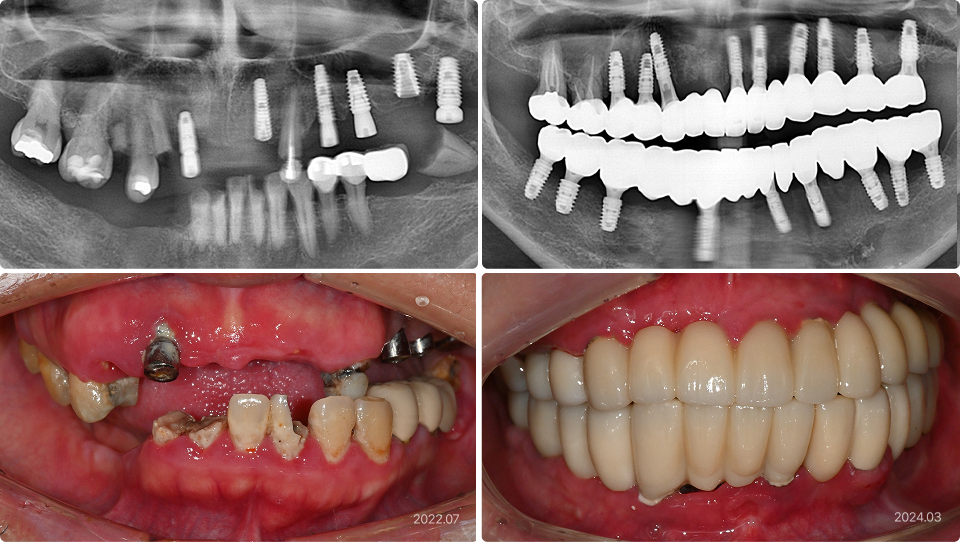

치과 공포증, 통증에 민감한 경우

“타 치과에서 치료받다가 치과 공포증이 너무 심해서 치료를 중단했어요.”

치료 전

치료 후

치료 내용

• 타병원에서 치료 중 치과 공포가 너무 심해서 중단하여 방치된 상태

• 의식하진정법(수면마취)으로 전체 임플란트, 뼈이식, 타치과 임플란트 보철 등 시행

• 이후 모든 치료를 수면 마취하에 수월하게 진행